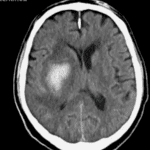

Ischemic Stroke

ICH